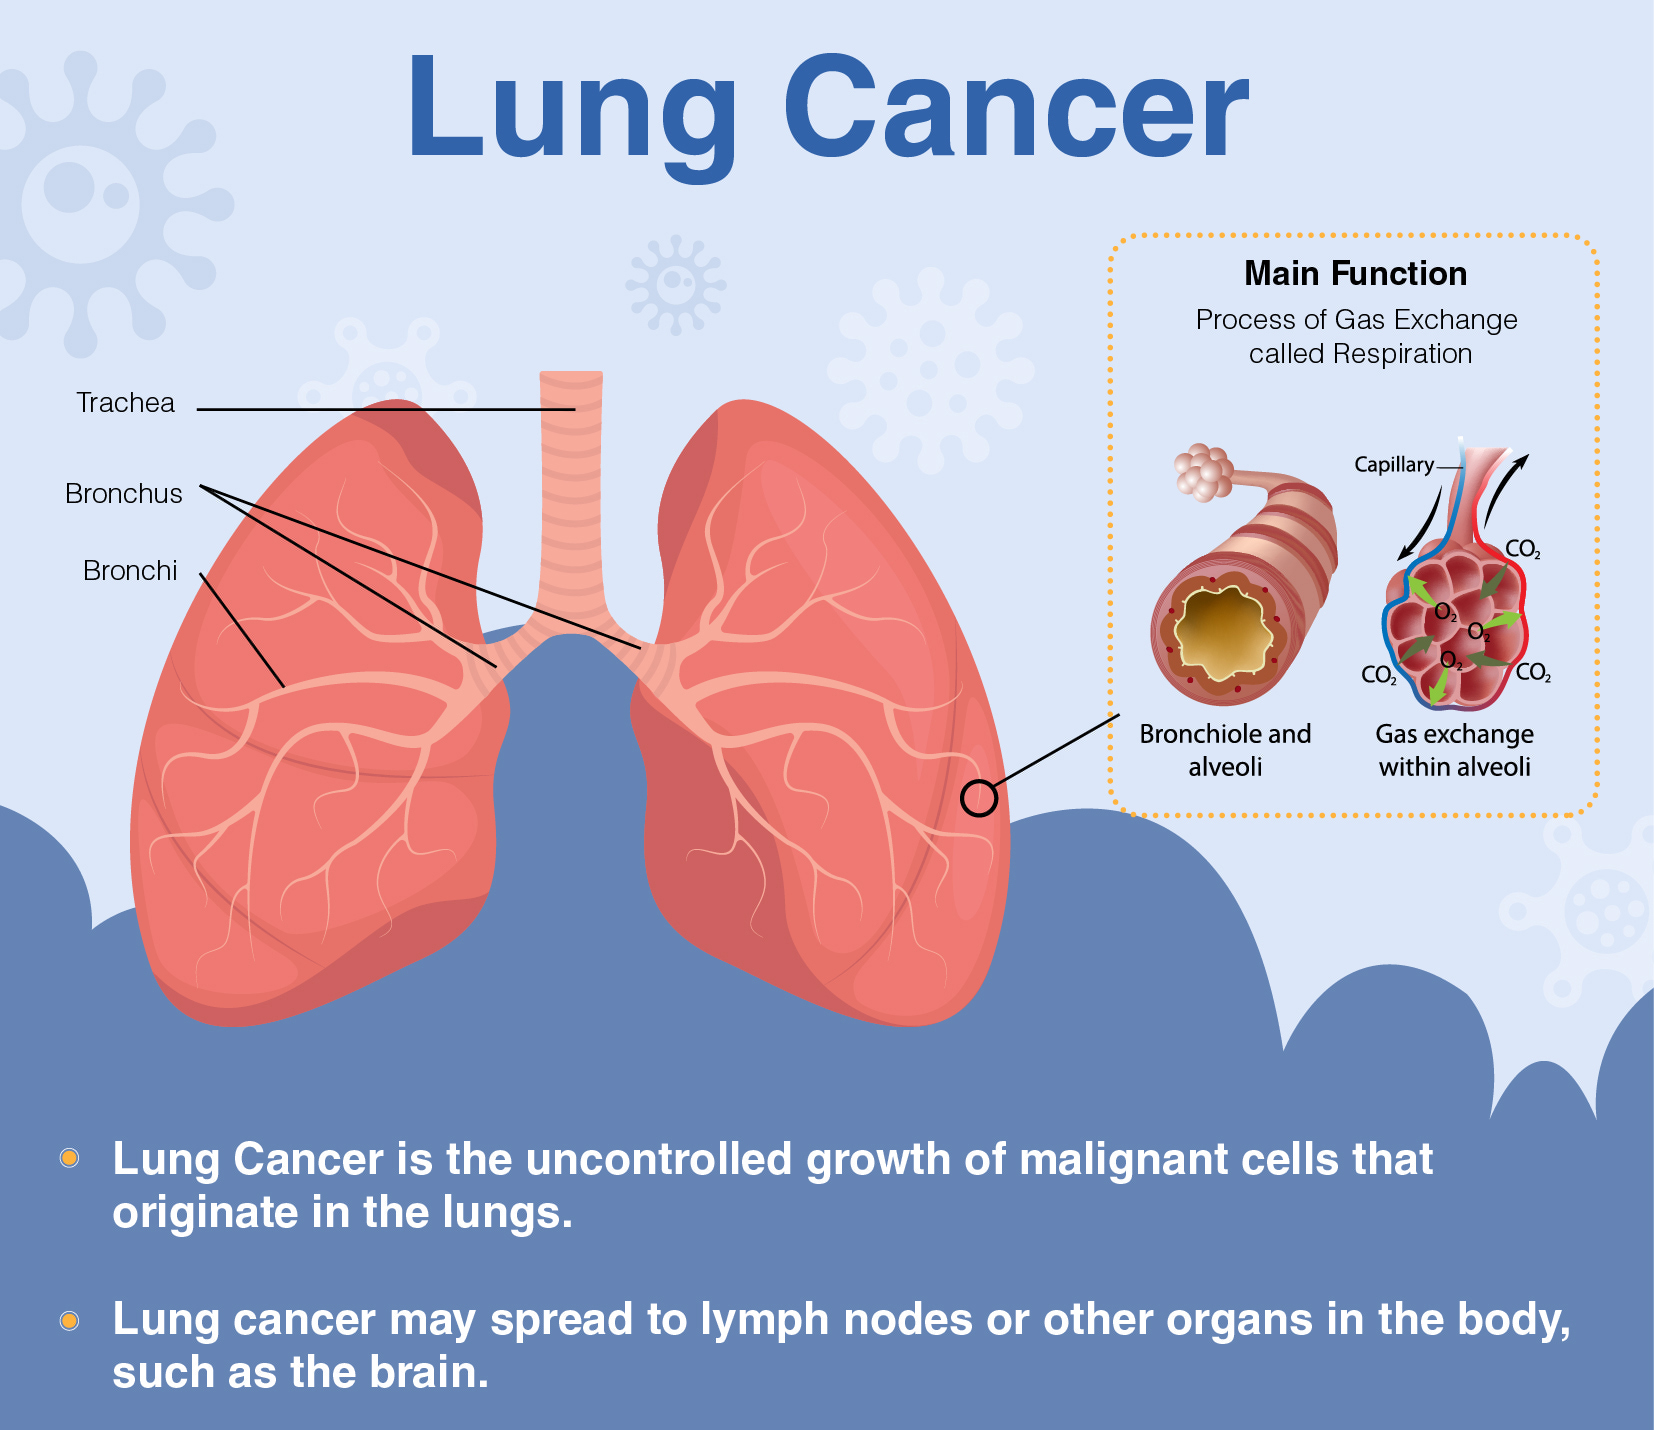

Lung cancer is cancer that starts in your lungs. The most important thing you can do to prevent lung cancer is to not start smoking, or to quit if you smoke. Lung cancer patient and advocate jill feldman takes pills at home that shrink tumors by blocking a signal that tells cancer cells to grow.

Staying active may help prevent certain cancers. Lung cancer is one of the most common cancers and has one of the lowest survival rates in the world. Excess weight results in the production and circulation of more.

People with small cell lung cancer are usually treated with radiation therapy and chemotherapy. Changing lifestyle or eating habits. It is the leading cause of cancer death among men and women.